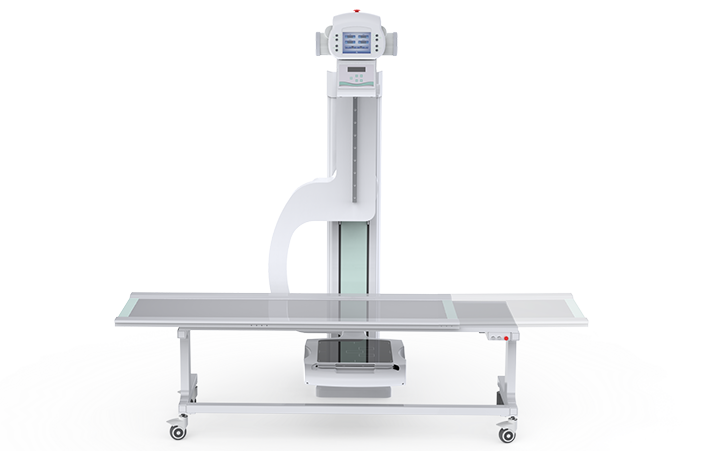

PLD7900

動(dòng)態(tài)U臂DR

多功能動(dòng)態(tài)平板DR,采用U型臂結(jié)構(gòu),具有靜態(tài)DR攝影、數(shù)字透視、數(shù)字造影和可視化攝影的功能。

注冊(cè)證編號(hào):粵械注準(zhǔn)20222060411